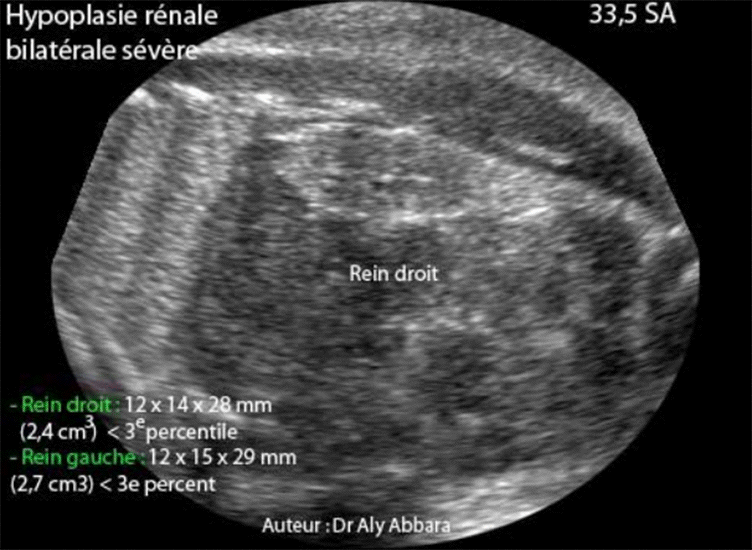

Hypoplasie rénale bilatérale foetale à 33,5 SA - Coupe échographie AP

Hypoplasie rénale fœtale bilatérale et sévère découverte à 33,5 SA

Coupes échographiques frontales des reins fœtaux hypoplasiques avec des images

échographiques permettant de les comparer aux reins normaux.

• Il s'agit d'une hypoplasie rénale fœtale bilatérale et sévère découverte fortuitement à 33,5 SA lors d'une exploration échographique dans le cadre du bilan systématique pour légère menace d'accouchement prématuré.

• L'échographie met en évidence la présence d'un anamnios avec deux petits reins hyper-échogènes :

• Rein gauche : 12 x 15 x 29 mm de diamètres avec volume évalué à (2,7 cm3) ce qui est largement inférieur au 3e percentile.

• Rein droit : 12 x 14 x 28 mm de diamètres avec volume évalué à (2,4 cm3) ce qui est largement inférieur au 3e percentile.